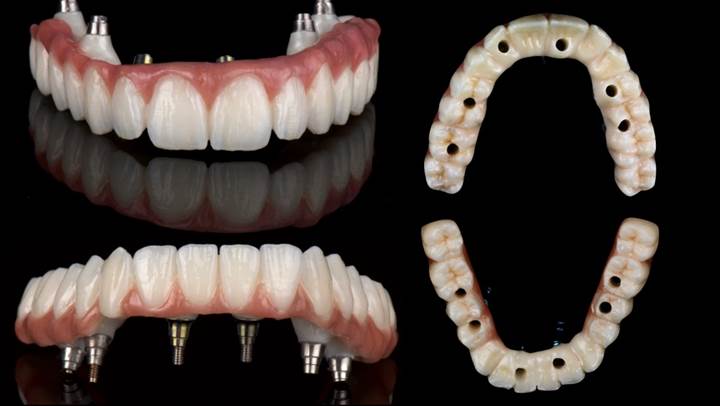

Clinical case: Full-mouth implants for mandibular & maxilla - restored using mixed prostheses

- Courtesy of Dr. Hyun Jun Kim, Korea -

Keywords

AnyRidge, full-mouth implants, mandibular, maxilla, edentulous, full mouth rehabilitation, Octa abutment, long-term clinical case, biological stability, Dr. Hyung Jun Kim

Products:

AnyRidge implant system